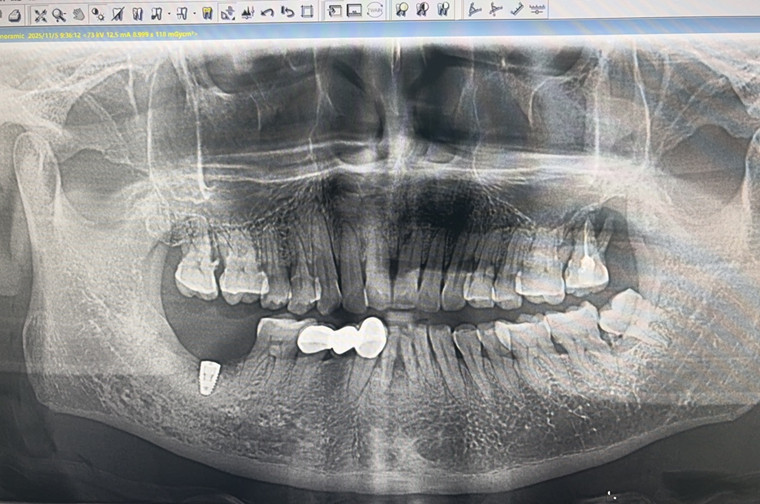

手术的一大亮点,是使用了由医院数字化设计中心陈旭医生团队自主研发的种植导板。据悉,该导板通过先进的3D设计软件,将患者的CBCT(锥形束CT)数据与口腔扫描数据精准融合,实现了从数字化设计到临床应用的完美转化,如同为手术安装了“高精度导航系统”。

上午9时整,手术直播准时开始。在严格的术前方案核对、规范的术区消毒铺巾后,手术在局部浸润麻醉下正式开始。邵丹院长首先将定制化的手术导板精准戴入患者口内,导板与牙列完美贴合。随后,手术进入核心阶段。邵院长通过导板预设的金属套管,使用专用钻头进行备洞操作。在导板的“导航”下,钻头严格遵循预设轨迹,彻底避免了传统手术中可能出现的角度和深度偏差。

在切口环节,他运用手术刀在牙槽嵴顶完成精准的弧形切口,最大限度地保护了患者的牙龈组织。从先锋钻定位、序列钻头扩孔,到种植体精准植入预设位置,整个过程一气呵成。术后即刻验证显示,种植体实际植入位置与术前数字化设计完全吻合。最终,手术以可吸收缝线的精细缝合画上句号,创口对合整齐,出血量极少。